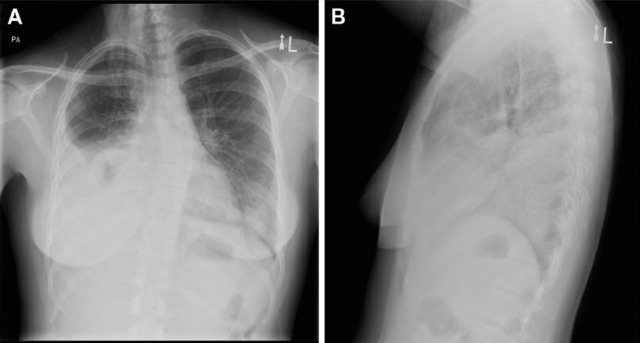

随后行胸腔穿刺术抽出血性胸水,胸水生化示葡萄糖 1.5 mmol/L,蛋白 51 g/L,乳酸脱氢酶 2212 U/L。胸水有核细胞总数 2100*106/L,仍以淋巴细胞为主(60%),格兰染色及培养均为阴性结果。胸片及胸部 CT 如图 1、2 所示。

图 1 A、B:正侧位胸片示右侧大量胸腔积液及肺不张